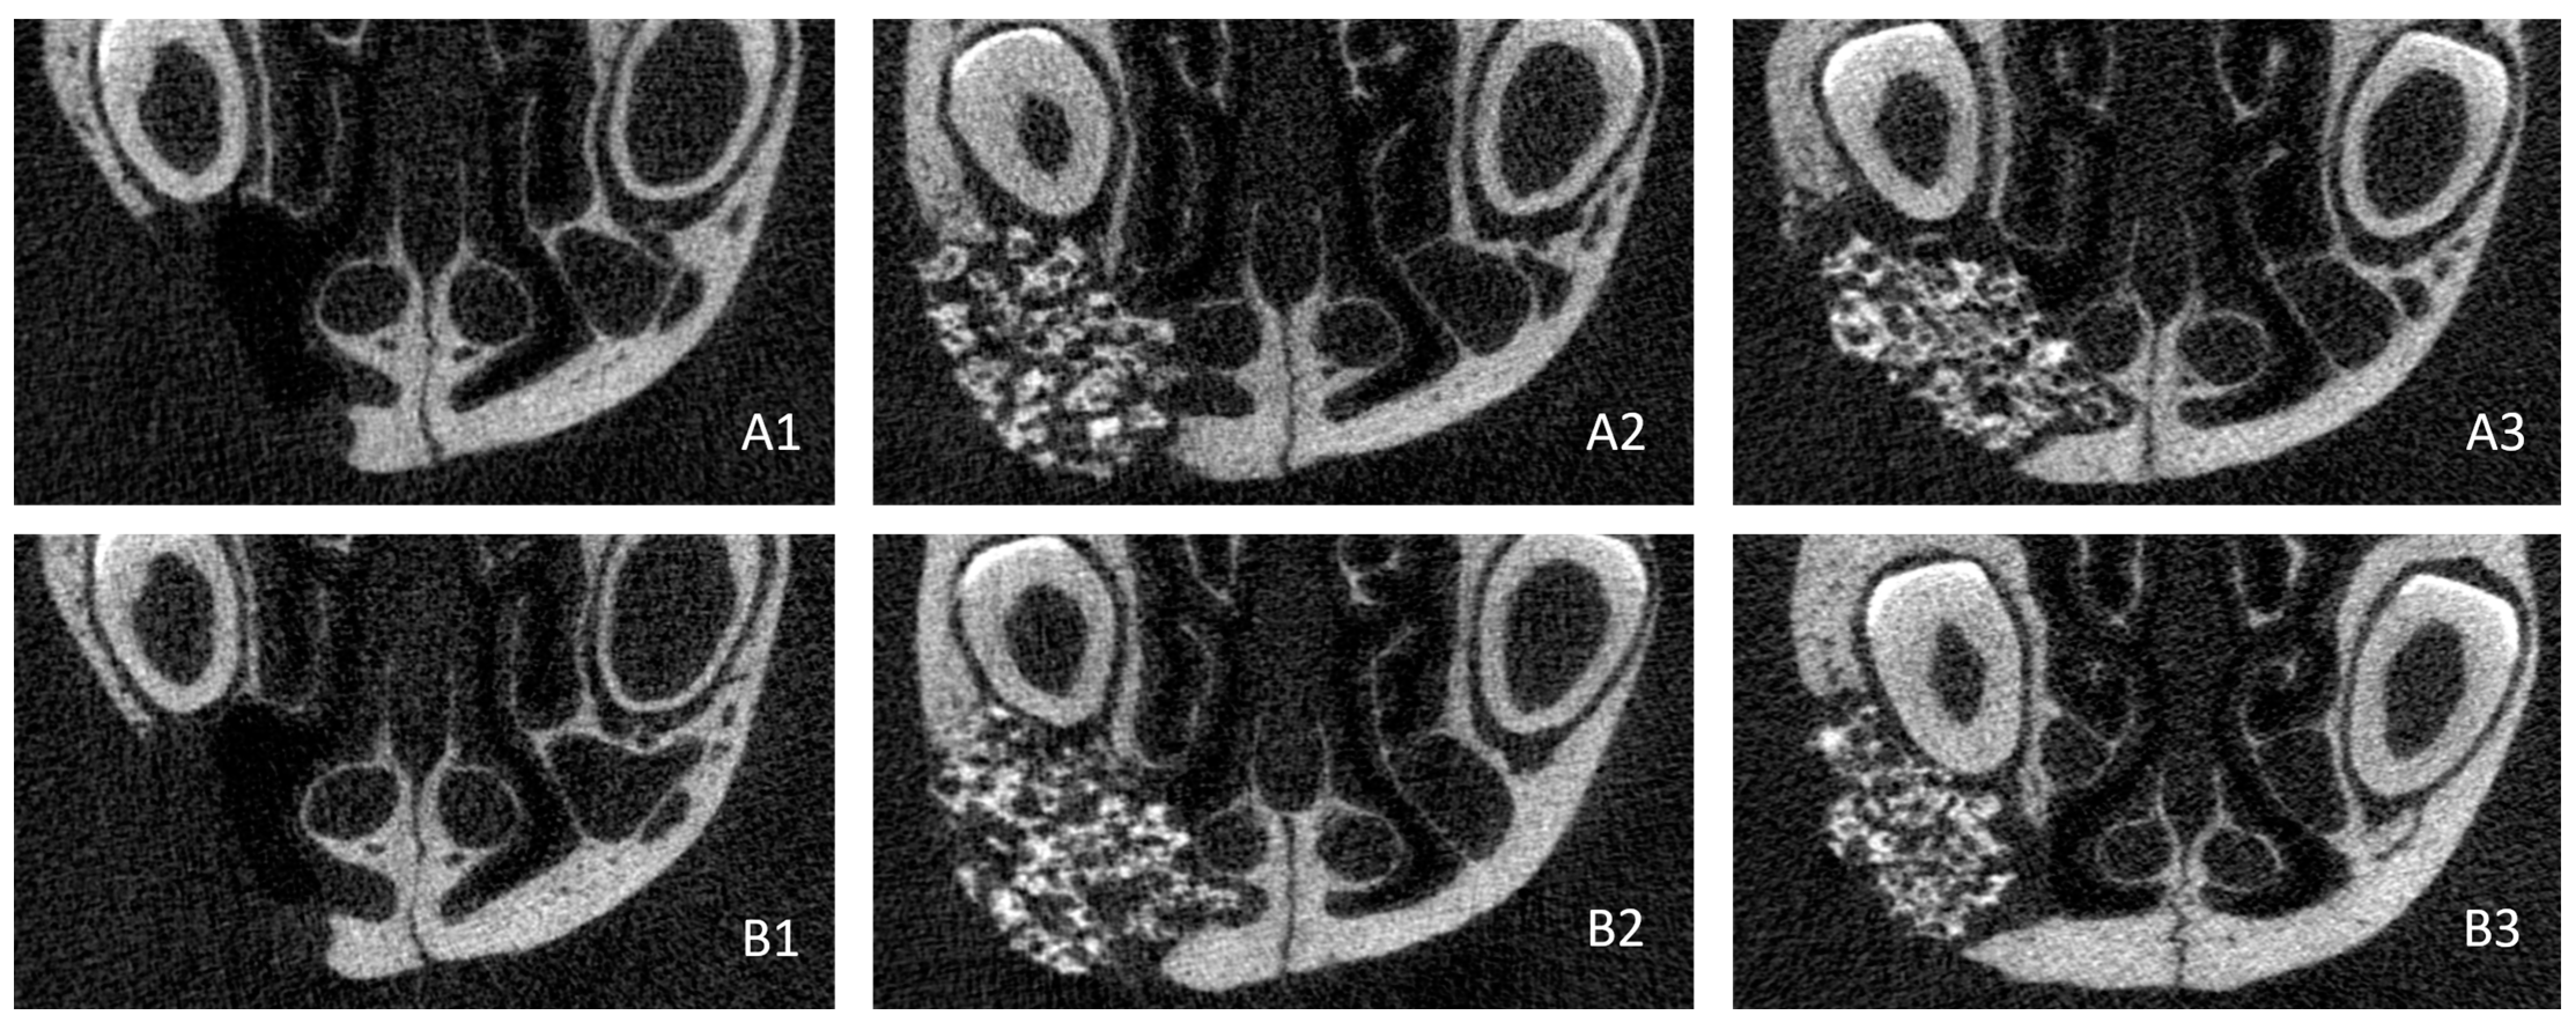

3.2.2. Computed Tomography Analysis

3.3. Bone Regeneration Study

3.3.1. Biomaterial Implantation

3.3.2. Computed Tomography Analysis

3.3.3. Bone Volume and Bone Mineral Density